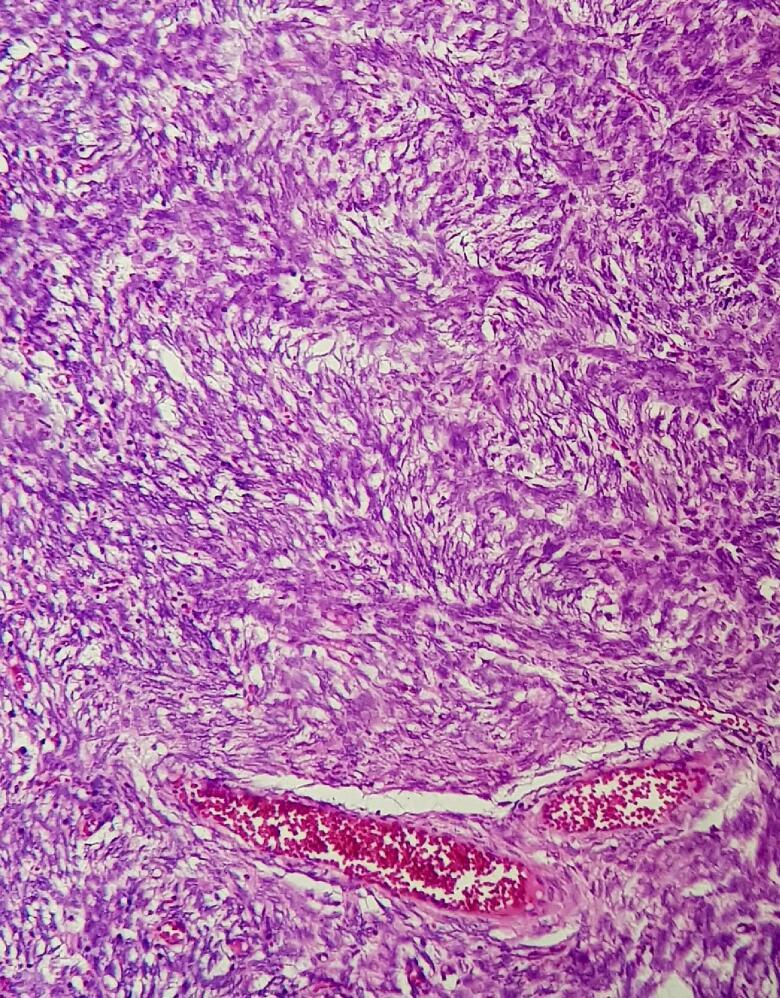

In this case study, we report a 52-year-old woman presenting with the chief complaint of unusual uterine bleeding. There was no specific finding in her past medical history. The CT study revealed enlarged bilateral ovary with a significantly large left ovarian mass and suspicious mass in uterus. By the diagnosis of ovarian mass, patient went under total abdominal hysterectomy with bilateral salpingo-oophorectomy (BSO), greater omentectomy, and appendectomy followed by post-op hormone therapy. Her follow-up was uneventful. The IHC and pathological study of samples revealed incidental LG-ESS uterus mass with metastasis to ovaries despite her primary diagnosis.

在本病例研究中,我们报告了一名52岁女性,主要主诉为异常子宫出血。她既往病史无特殊发现。CT检查显示双侧卵巢增大,左侧卵巢有一个明显较大的肿块,子宫内有可疑肿块。通过卵巢肿块诊断,患者接受了全腹子宫切除术、双侧输卵管卵巢切除术(BSO)、大网膜切除术和阑尾切除术,随后进行术后激素治疗。她的随访情况良好。样本的免疫组化(IHC)和病理研究显示,尽管她最初的诊断并非如此,但偶然发现子宫肿块为LG-ESS并伴有卵巢转移。